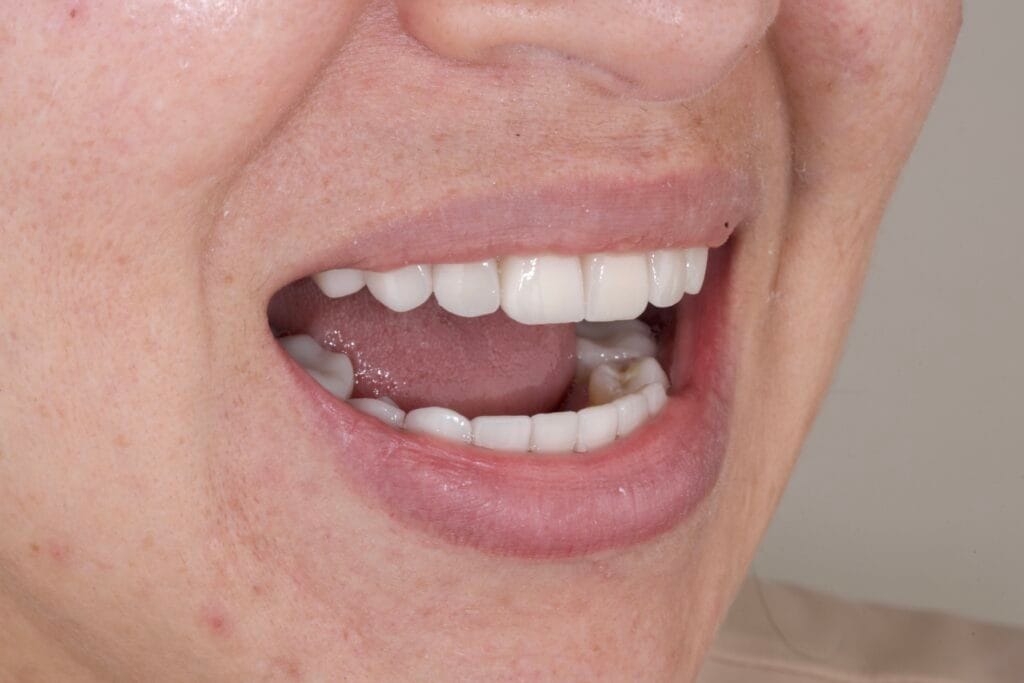

For this transformation, Dr. Paola Zabaleta selected lithium disilicate as the restorative material. This choice was based on its excellent optical properties, strength, and ability to mimic natural enamel.

The color, translucency, and morphology were fully customized, with the patient actively involved in every decision. This collaborative process ensures satisfaction and long-term success.

Personalized Design Leads to Natural Results

Every detail in this case was tailored to the patient. From tooth shape to shade selection, the final smile reflects her preferences while respecting her facial structure.

The result is a smile that looks effortless, balanced, and timeless.